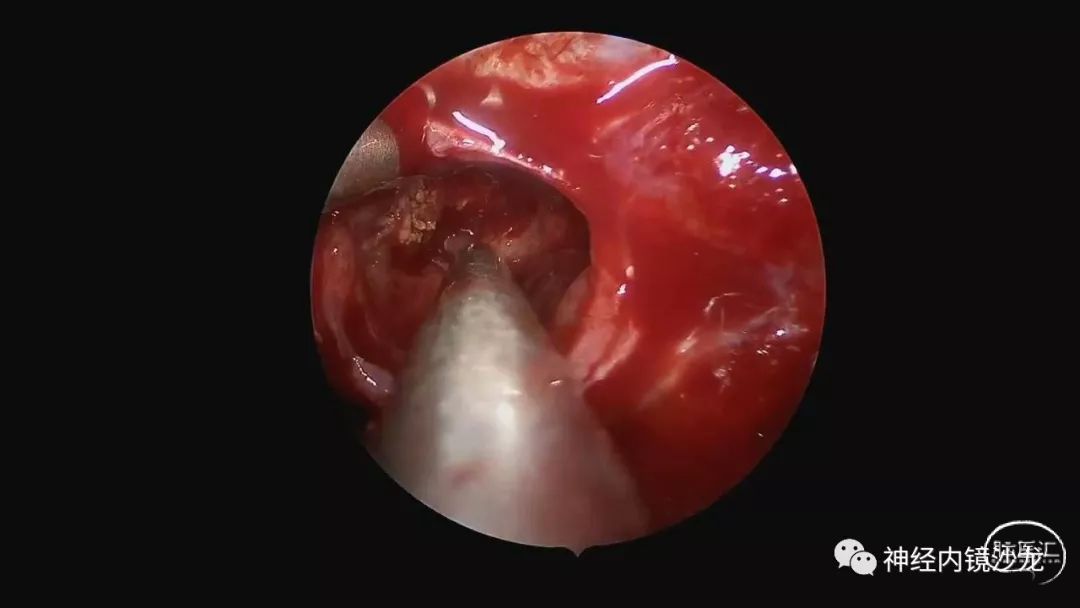

精彩图表

从事神经外科十余年,擅长神经外科肿瘤诊治,尤其是神经内镜微创手术治疗垂体瘤、颅咽管瘤、脑膜瘤等颅底肿瘤